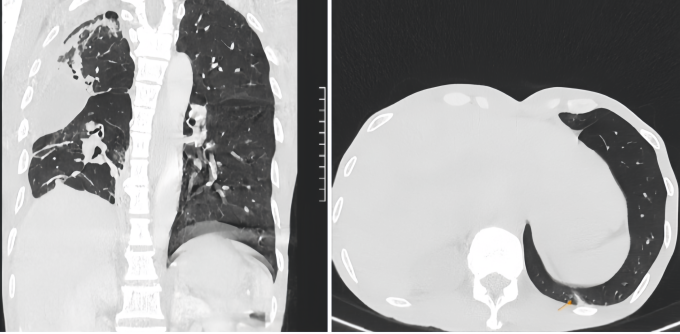

Kết quả chụp CT tại Bệnh viện Đa khoa Tâm Anh TP HCM cho thấy ổ mủ 4 cm chèn ép làm xẹp phổi bệnh nhân gây suy hô hấp cấp tính. Mủ tích tụ tạo ra ổ nhiễm khuẩn khiến người bệnh khó thở, ho ra máu.

PGS.TS.BS Vũ Hữu Vĩnh, Giám đốc Trung tâm Ngoại Lồng ngực - Mạch máu, chẩn đoán anh Tuân bị nấm phổi và lao phổi, là nguyên nhân chính dẫn đến suy hô hấp. Phổi tổn thương sẽ để lại sẹo, một bào tử nấm Aspergillus nhỏ cũng có thể ký sinh tạo hang, hình thành khối u nấm, ổ áp xe tàn phá lá phổi.

Êkíp mổ ghi nhận toàn bộ phổi phải người bệnh đã bị mủ tàn phá gây đông đặc, mùi hôi nặng từ ổ vi khuẩn kỵ khí lâu ngày. Khối u nấm xâm lấn trực tiếp vào các động mạch và mạch máu lớn, khiến chúng dính chặt vào nhau, gây khó khăn cho việc bóc tách. Sau hơn 4 giờ, êkíp hút gần một lít dịch mủ ra khỏi phổi anh Tuân, rửa sạch lồng ngực, cắt bỏ phần phổi hoại tử, bảo tồn tối đa nhu mô phổi lành và tạo hình phế quản để phục hồi lưu thông không khí.